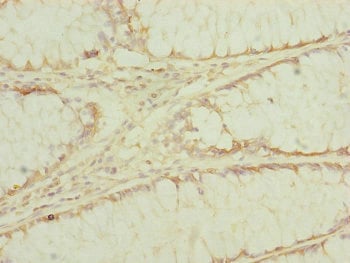

IHC (Immunohiostchemistry)

(Immunohistochemistry of paraffin-embedded human colon cancer using AAA231607 at dilution of 1:100)